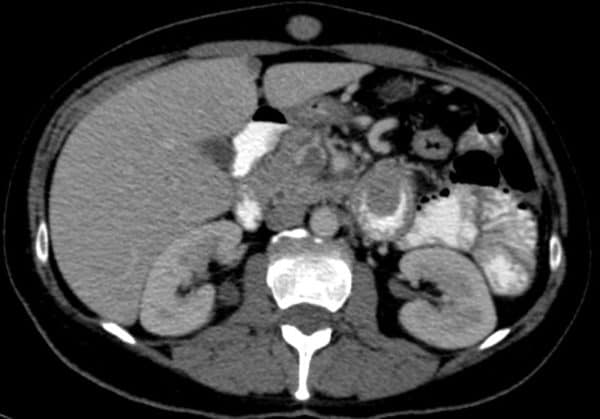

Di căn ruột non - Ảnh 3

Di căn ruột non

» Thông tin: Nữ giới – 56 tuổi.

» Lâm sàng: Đau bụng.